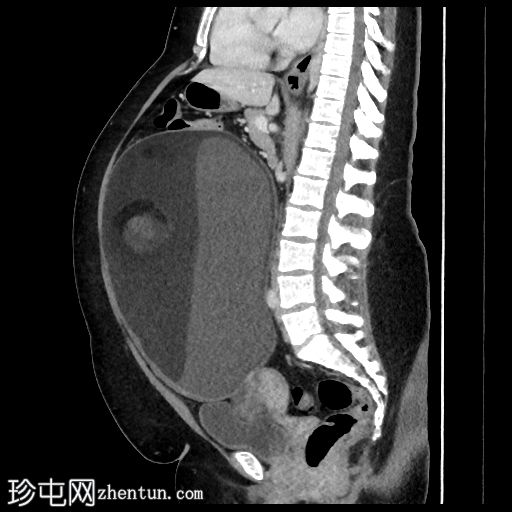

矢状位增强扫描(门静脉期)

盆腹腔巨大囊性病变,可见脂肪液平面及漂浮球征(脂肪/软组织团块漂浮)

病变周边可见钙化灶

左侧附件呈旋涡状外观,提示附件扭转

以上影像学表现提示左侧卵巢成熟囊性畸胎瘤伴附件扭转